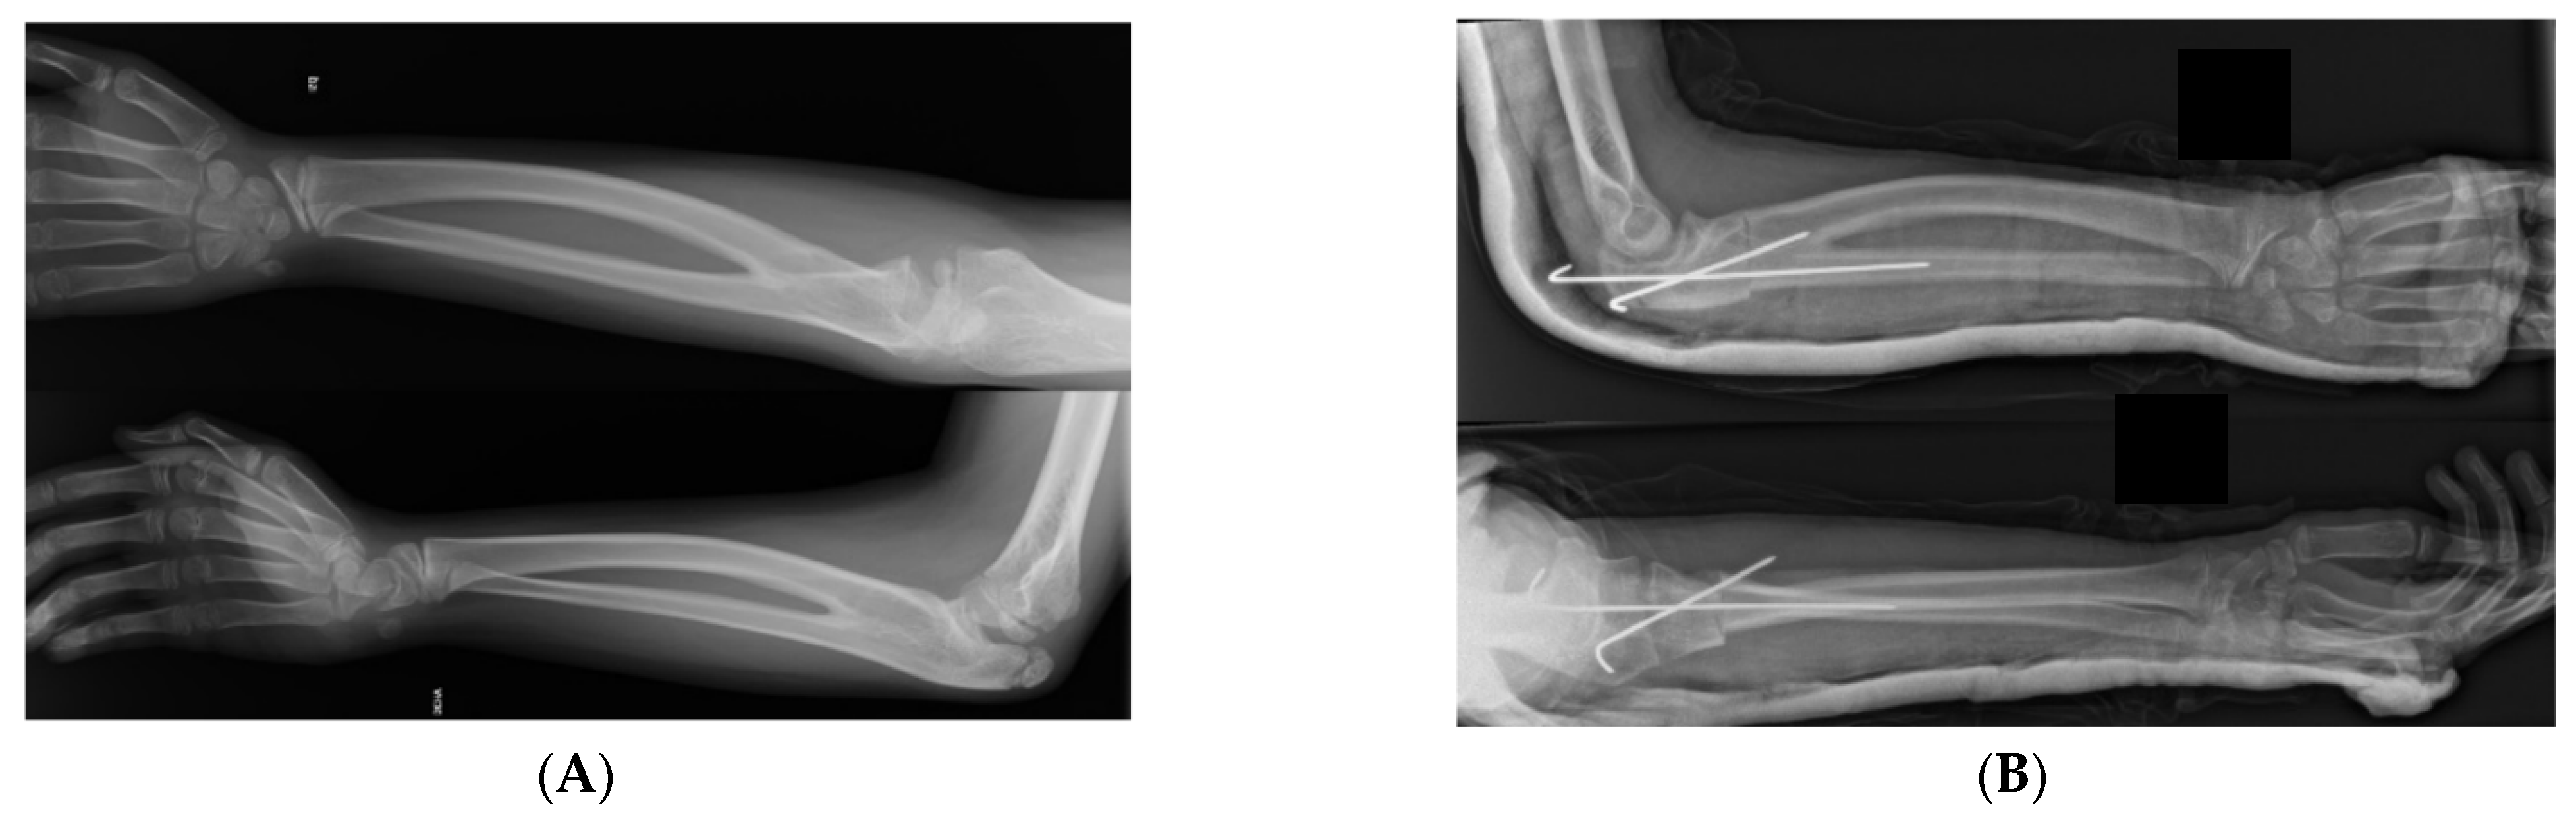

Surgery is a common treatment for symptomatic patients with CRUS (Figure 1), but it is not required for most patients unless they have limitations of daily life activities. Mild deformity, minimal functional deficit (<60° of pronation), and adaptations developed for activities are contraindications for surgical procedures [3]. However, surgical treatment would be desirable in bilateral congenital radioulnar synostosis (CRUS) or in patients with a forearm fixed in more than 60° of pronation. The optimal age for surgical treatment is before school age, when the robust periosteum can support the cut radius and facilitate callus formation; thus, nerves and blood vessels can tolerate torsional deformity, avoiding vascular and postoperative complications [3,23].

Figure 1.

(A) Bilateral congenital radioulnar synostosis. Preoperative X-ray. (B) Osteotomy through the synostosis going simple and easy to fix with 2 KW. Postoperative X-ray.

There are various types of osteotomies and fixation methods for CRUS. The standard is the osteotomy through the synostosis, going simple and easy to fix with 2 KW. The main complication might be compartmenting syndrome because of the torsion of the forearm soft tissues; thus, the patient should stay overnight. In older patients, as they have more rigid tissues, a segment of the synostosis might be respected in order to decrease forearm pressure after torsion. Fascia release might be indicated also. Osteotomy of both bones (radius and ulna) at different levels has favorable outcomes but necessitates two surgical scars and fixation with nails (with the associated risk of penetrating the growth plate) [29]. The advantages of a single osteotomy (either radius or ulna) over a double one include surgery simplicity with minimal complications and surgical scars [27]. A highly feared complication during the rotation process, aside from compartment syndrome, is the injury to the posterior interosseous nerve, as described by Hung et al. [28].